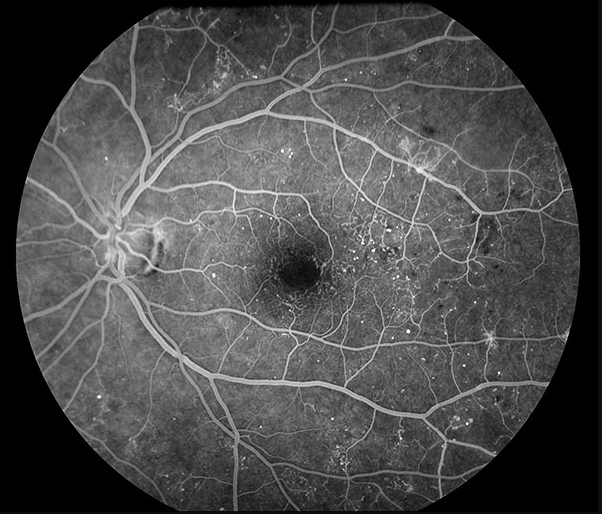

진단: 안저검사 또는 FAG에서 **신생혈관(neovascularization)**이 확인되면 PDR로 진단합니다. 망막 허혈에 의한 VEGF 상승이 원인이며, NPDR 단계에서는 보이지 않던 비정상적 새 혈관이 망막 표면/시신경유두/홍채에 발생하는 것이 핵심 소견입니다.

DME (당뇨황반부종)

진단: OCT에서 황반부 망막 두께 증가(중심와 두께, CST 증가) 또는 안저검사에서 황반부 부종/경성삼출물이 확인될 때 진단합니다. NPDR/PDR 어느 단계에서든 동반 가능하며, 당뇨망막병증에서 시력저하의 가장 흔한 원인입니다.

- OCT: DME 평가의 gold standard. CST, 망막내/하액 평가

- FAG (Fluorescein Angiography): 비관류 영역, 미세동맥류 누출, 신생혈관 확인